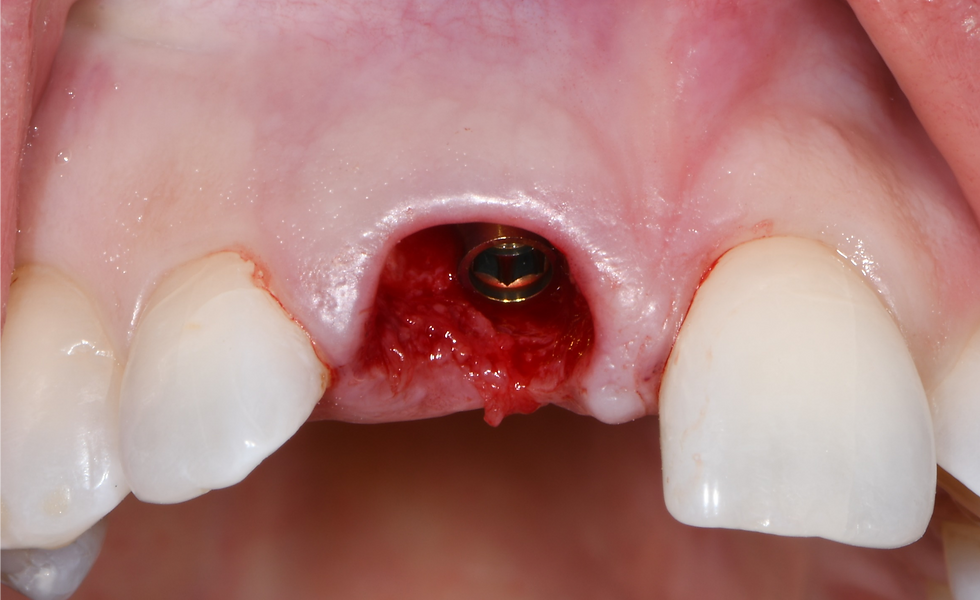

Implant placed in the post-extraction socket

The gap is filled with a particulate bone graft of porcine origin